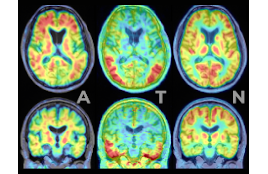

CAMDでは2014年にアルツハイマー病におけるアミロイドの脳内蓄積を予測する血液バイオマーカーを世界に先駆けて発見し、新しい研究の扉を開きました(Nakamura et al. Nature. 2018)。今日、認知症血液バイオマーカーの開発は世界でも最もホットな研究分野です。CAMDではアルツハイマー病のみならず、他の認知症疾患のバイオマーカー、認知症の超早期からのバイオマーカーなどを全国の研究者とともに研究を進めています。認知症バイオマーカーは、認知症の診断や予防に革新を及ぼす技術であり、国立長寿医療研究センターの臨床部門(もの忘れセンター)とともに、その研究成果を皆様に一日でも早くお届けできるよう努力を重ねてまいります。

一方、認知症の進行を止める治療薬(病態修飾薬)はいまだ開発されていません。認知症の発症には、遺伝的因子に加え、生活習慣病などの多くの後天的因子が関与しています。中枢神経における炎症や代謝異常、血管障害、シナプス機能から脳のネットワーク障害などの新たな視点からも研究を進めています。また、治療薬ではなくライフスタイルの改善による認知症予防の可能性を検証するため、2019年から認知症リスクのある高齢者を対象とした多因子介入試験を行っています(J-MINT研究)。最新のテクノロジーを駆使して、認知症の予防・治療法の開発に取り組んでいます。

| 2026年2月19日 | アルツハイマー病の進行期の断片型Aβやタウの脳内の分布は、カテプシンやジペプチジルペプチダーゼとよく類似する |